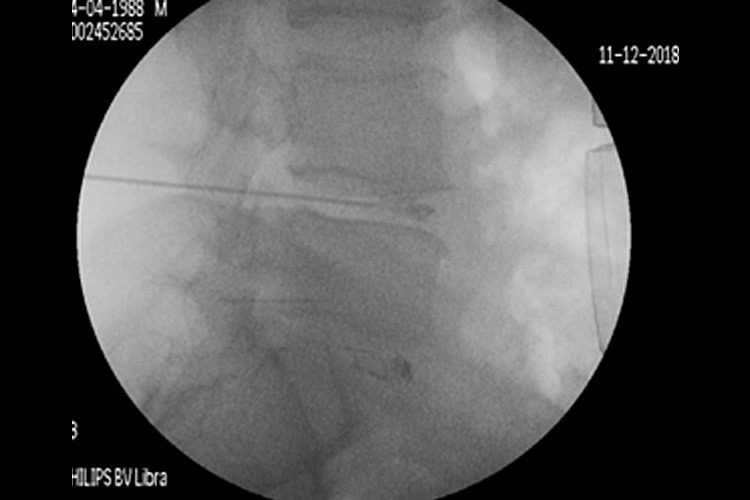

Με τον δεύτερο τρόπο γίνεται, υπό ακτινοσκοπικό έλεγχο, διαδερμική έγχυση ενός υλικού που έχει μορφή γέλης (gel) και συνίσταται από αιθανόλη, παράγωγα κυτταρίνης και ακτινοσκιερό υλικό tungsten. Η έγχυση γίνεται στο κέντρο του δίσκου, μέσα από έναν οδηγό και λειτουργεί άμεσα. Η δράση του διαλύματος στηρίζεται στις φυσικοχημικές ιδιότητές του: απορροφητική επίδραση της αιθανόλης με το νερό, που περιέχεται στον δίσκο, σε συνδυασμό με ένα φαινόμενο ώσμωσης- αφυδάτωσης του δίσκου από την περιφέρειά του προς τον πυρήνα του. Έτσι, «απορροφάται» η προβολή του δίσκου πίσω προς το κέντρο του (σχ.4).

Περίπτωση 2: Ακτινοσκόπηση σε Διαδερμική Δισκοπλαστική με χρήση ενδοδισκικού υλικού Discogel σε κήλη μεσοσπονδυλίου δίσκου Ο4-Ο5.